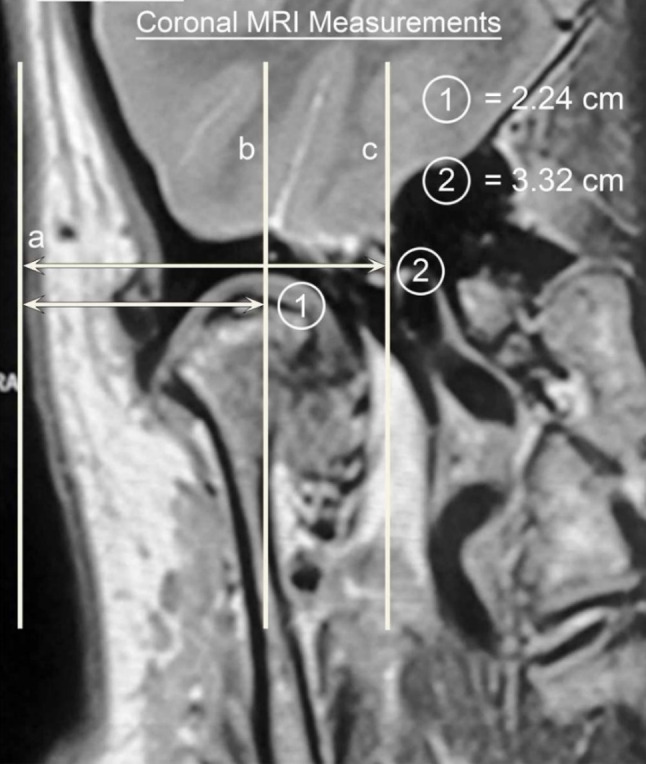

The coronal scans are next examined and measured for the depth of penetration (Figs. 3, 4).

Fig. 4.

Coronal measures superimposed on the MRI

Vertical lines are drawn at the level of the upper joint space parallel to the skin (Line a), through the mid-condyle (Line b) and to the most medial aspect of the mandibular condyle (Line c). A horizontal line perpendicular to Line (a) is drawn to the mid-condyle and measured in mm, (Line 1) and a second measurement is mm from the skin to medial condyle (Line 2).

The mid-condyle measurements determine the usual working depth and the medial condylar depth the penetration depth beyond which one must not go.